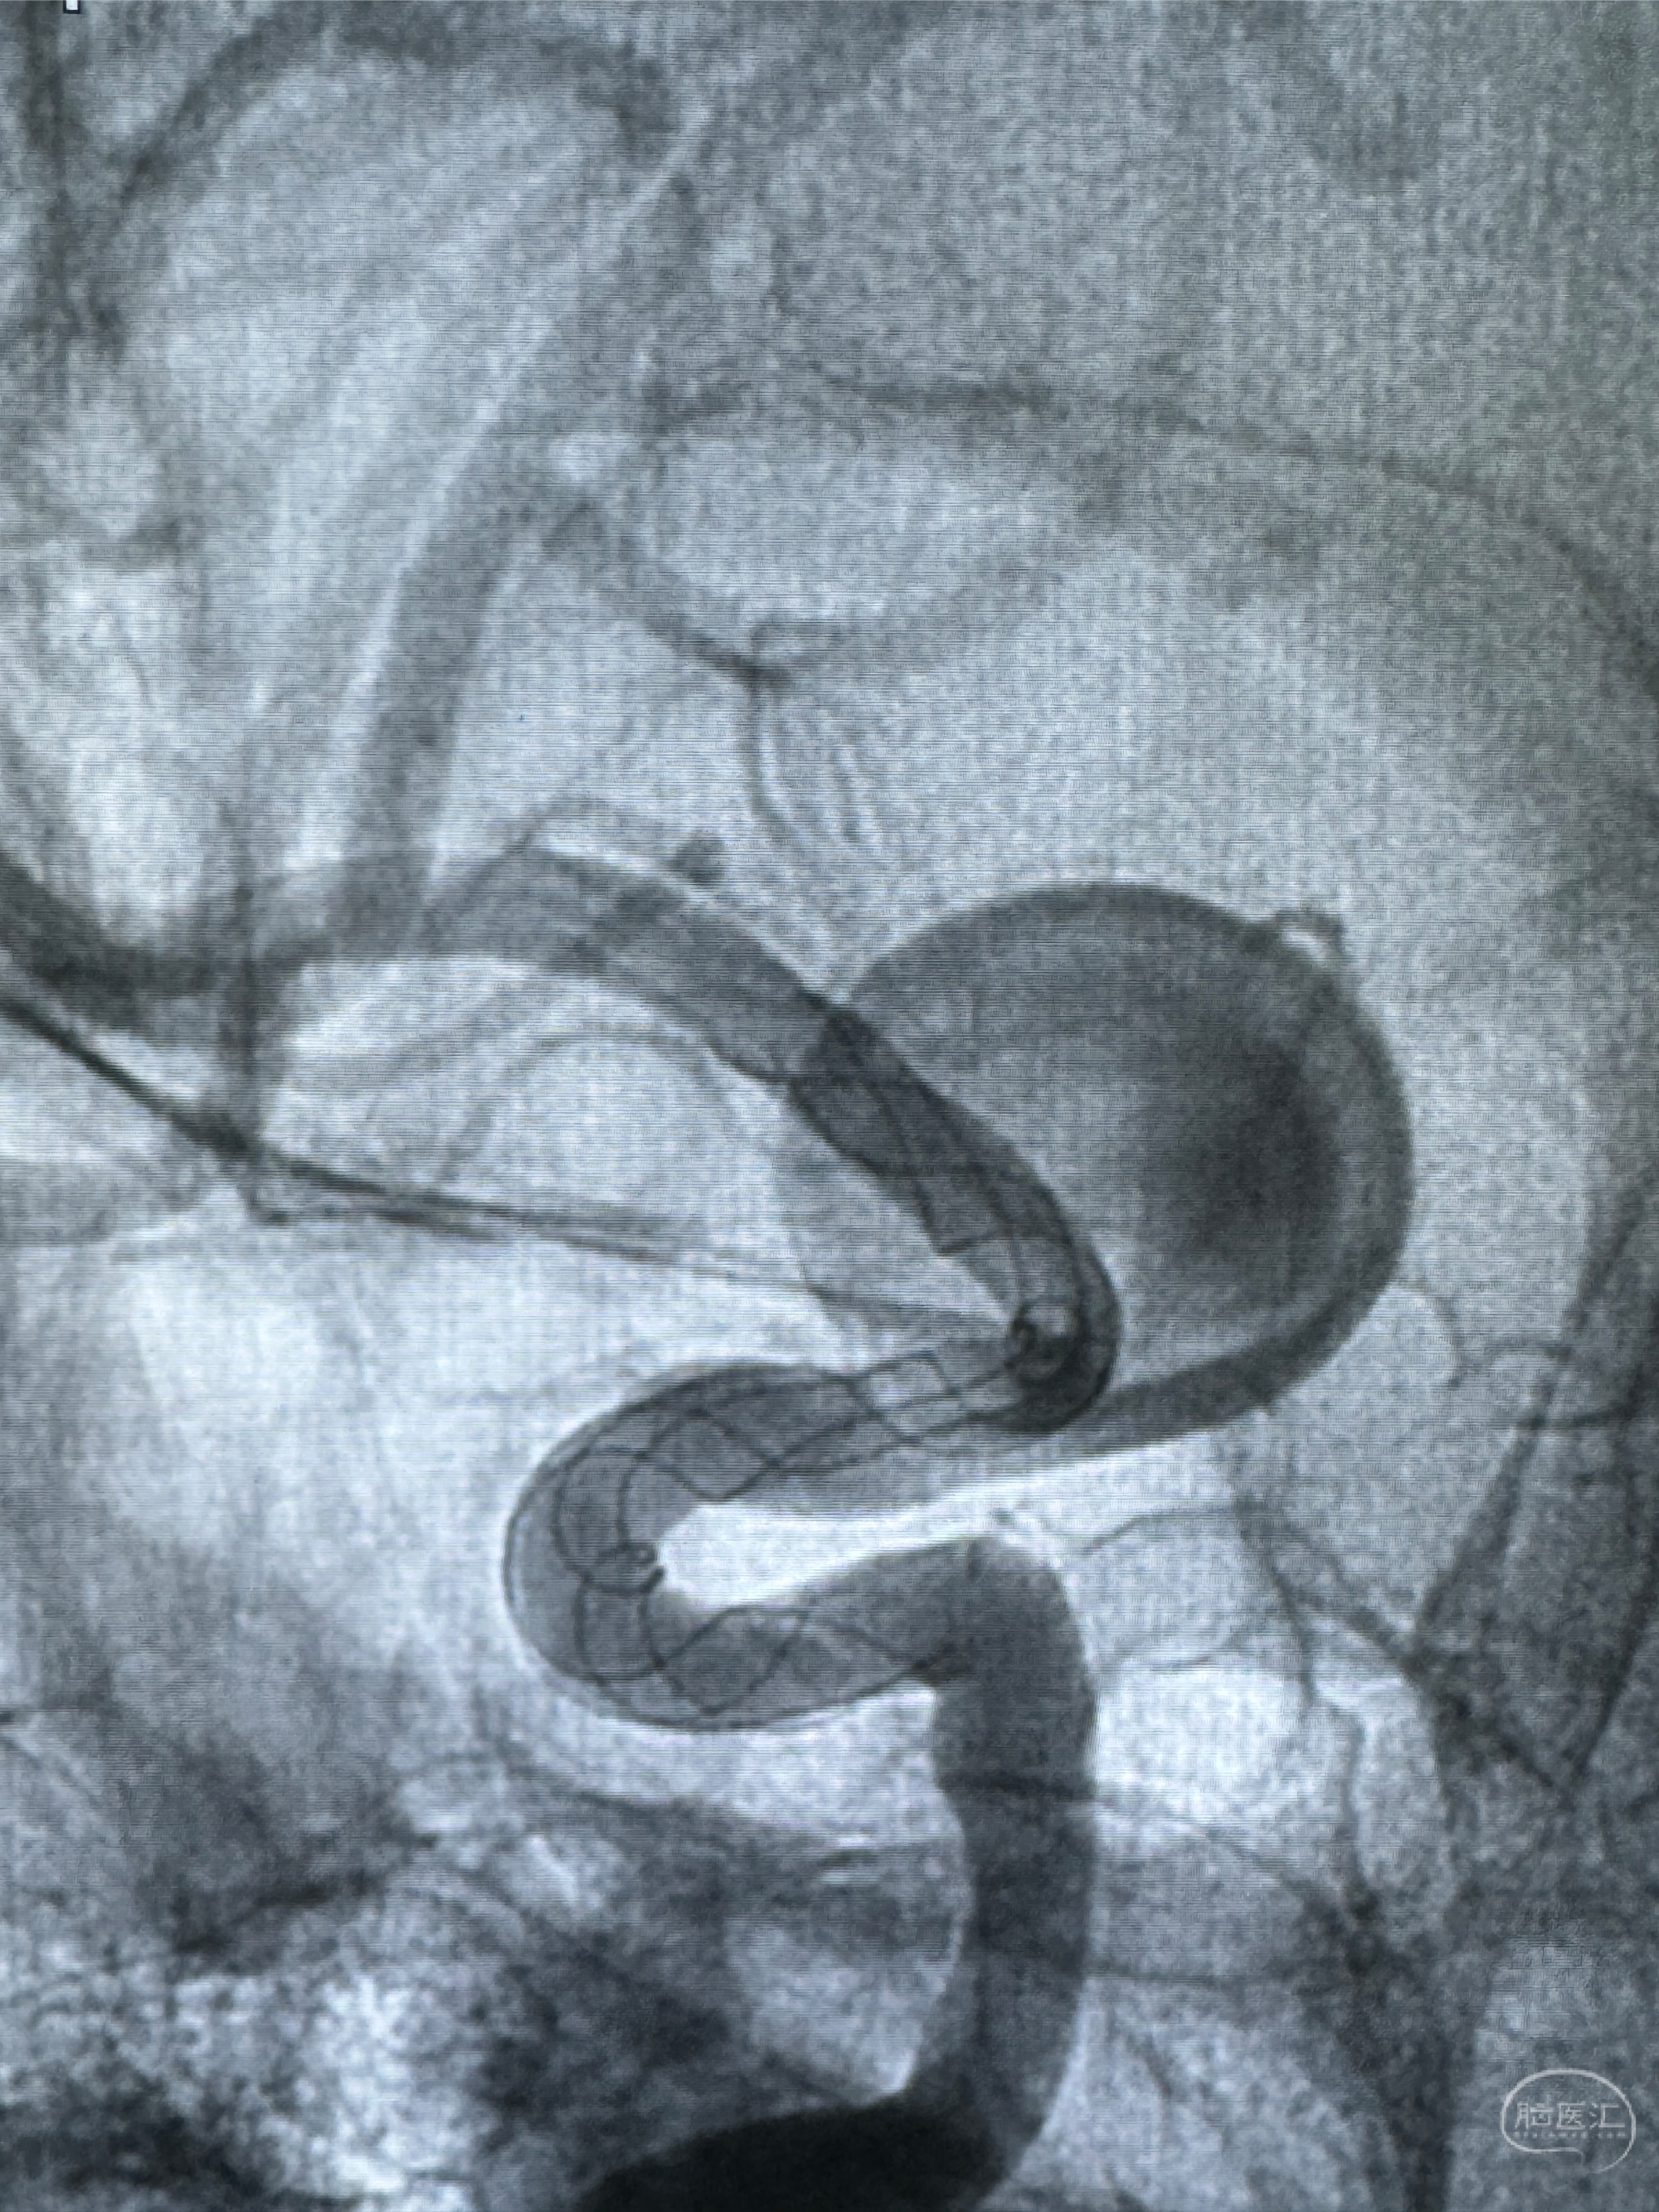

透视可见红圈部分为支架导管的头端

手推冒烟显示支架位置及展开情况,箭头为支架导管的位置

尝试回收支架失败,只能考虑释放支架了

逐帧图像展示歪着脖子释放支架,旁边吩咐助手手机摄影、拍照留像(透视机不能留影像)

看动脉瘤内造影剂滞留,未见明确射流,遂撤出预留的栓塞微导管,快速结束手术,经导引导管灌注替罗非班250ug。